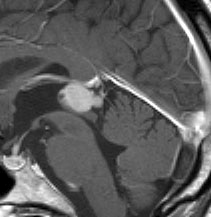

これは若い女性に見つかった松果体細胞腫です。無症状ですし水頭症もありません。松果体のう胞との区別がむずかしいのですが,嚢胞の壁が厚くて造影剤で強く増強されていることから,松果体のう胞ではないことがわかります。手術で完全に摘出して治りました。松果体細胞腫はゆっくり大きくなる良性の腫瘍です(WHOグレード1)。周りの脳に浸潤しないので手術は比較的安全にできますし,全部取れます。